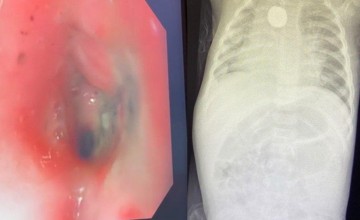

وأضاف بأنه نظرا لعدم استجابة الحالة للعلاجات جرى تكوين فريق طبي لدراسة حالة الطفلة وبعد عمل الفحوصات وأشعة للدماغ وتخطيط لكهرباء الدماغ وغيرها من الفحوصات اللازمة من قبل فريق مخ وأعصاب الأطفال وفريق جراحة الأعصاب تم اتخاذ قرار بالتدخل الجراحي.

وبين التجمع أن العملية تكللت بالنجاح بالرغم من صعوبتها ودقتها حيث يتم الزراعة في العصب الحائر بالقرب من الشريان السباتي الباطن والوريد الوداجي وهي “أوعية دموية رئيسية للدماغ”، دون حدوث أي مضاعفات أو مخاطر أثناء وبعد العملية التي استغرقت ساعتين وخرجت الطفلة وهي تتمتع بصحة جيدة.